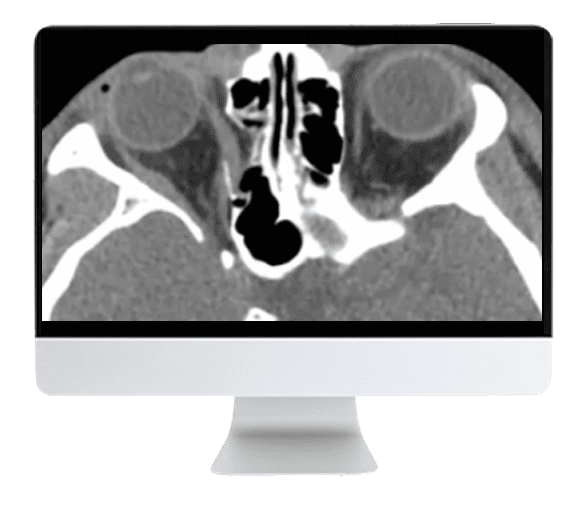

The ARRS Imaging Victims of Violence: Fists, Stabs, Bullets, and Blasts 2021 (CME VIDEOS) is designed to empower radiologists and medical professionals with the essential imaging knowledge required for evaluating victims of violence. From unarmed confrontations to complex explosive trauma, this comprehensive course provides in-depth guidance on recognizing both common and atypical imaging findings associated with various mechanisms of injury, including physical altercations, penetrating trauma, gunshot wounds, and blast injuries. The curriculum also covers the radiologist’s pivotal role in Mass Casualty Activations, preparing you for effective response in high-stakes situations. Experience world-class medical learning — accessible anytime, anywhere — and elevate your ability to optimize trauma patient care.